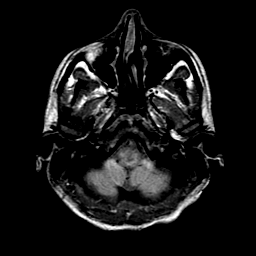

Sarcoma, MR Study #1 mr-pd -- Slice #2

[Home][Help][Clinical] Slice 2